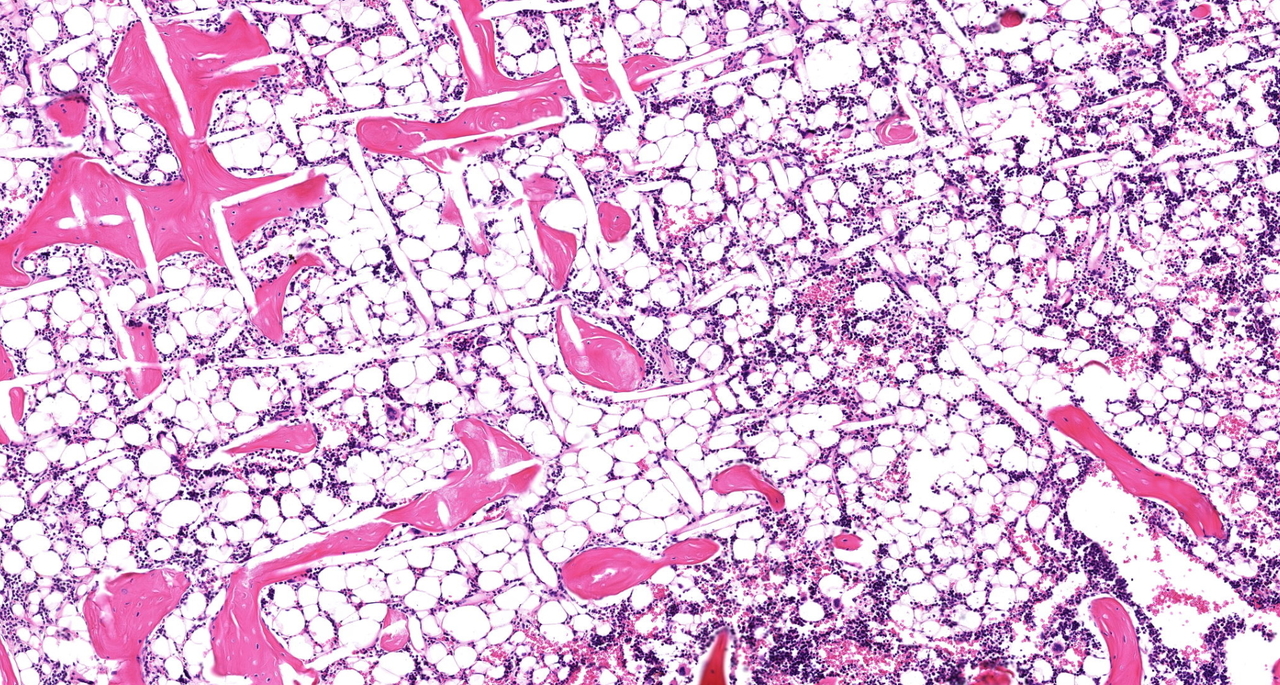

In our recent Communications Biology manuscript, we investigated the role the microenvironment plays in shaping tumor growth and subsequent bone metastasis. Harnessing tissue engineering techniques, we generated two tiers of humanization within an immunocompromised murine model: the primary prostate tumor with TME, and the bone organ as a metastatic site. Using androgen-sensitive human prostate adenocarcinoma cells derived from the left supraclavicular lymph node metastasis from a 50-year-old male (LNCaP) and an androgen insensitive cell line (PC-3) which was established in 1979 from bone metastasis of grade IV of prostate cancer in a 62-year-old patient. We demonstrated that the TME influences bone tropism in a manner specific to the cells with low (LNCAP) and high (PC-3) metastatic potential.

The primary TME is an agent for prostate cancer development, growth, progression, and metastasis. However, the TME is also a complex and multifaceted entity and there is great difficulty in delineating the contributing roles of specific TME components in this context. To build on our extensive program engineering bone microenvironments to study cancer cell bone tropism, our team engineered a primary prostate tumor using prostate cancer cell lines and two critical TME cell types: cancer-associated fibroblasts (CAFs) and microvascular endothelial cells (MVECs). Both CAFs and MVECs have been implicated in directly contributing to prostate cancer metastasis5,6.

In our current manuscript published in Communications Biology, we created a humanized prostate TME consisting of either the LNCaP or PC-3 prostate cancer cell line grown together with CAFs and MVECs in an orthotopic environment. Both the LNCaP- and PC-3-derived tumors developed and metastasized over a 10-11-week period. Interestingly, the humanized TME showed a trend to decrease metastasis of PC-3 cells to humanized bone but did not influence metastasis to the murine bones or visceral organs. In contrast, the humanized TME enhanced LNCaP primary tumor growth and bone metastasis. Our exciting results uncovers a potential new role of the TME in prostate cancer osteotropism which warrants further investigation.